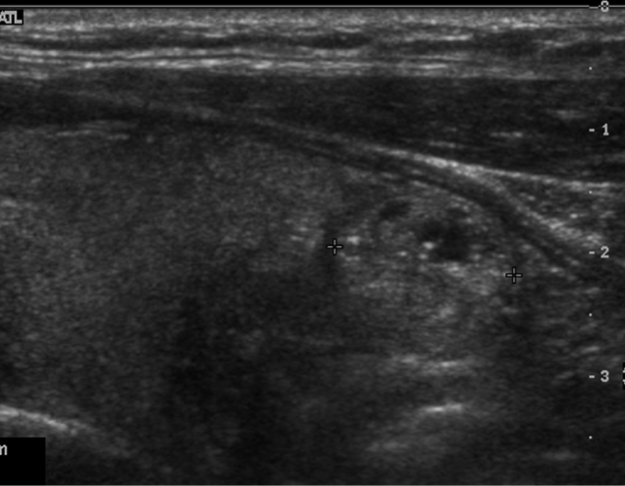

Solid nodule

Dx?